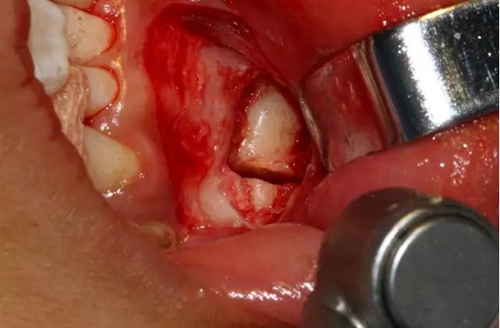

切開、翻瓣

去除骨皮質(zhì),暴露牙冠大部分

設(shè)計(jì)冠切的位置

橫斷牙冠,注意深度的把控

為了減少骨創(chuàng),“T”型分割牙冠

去除冠部